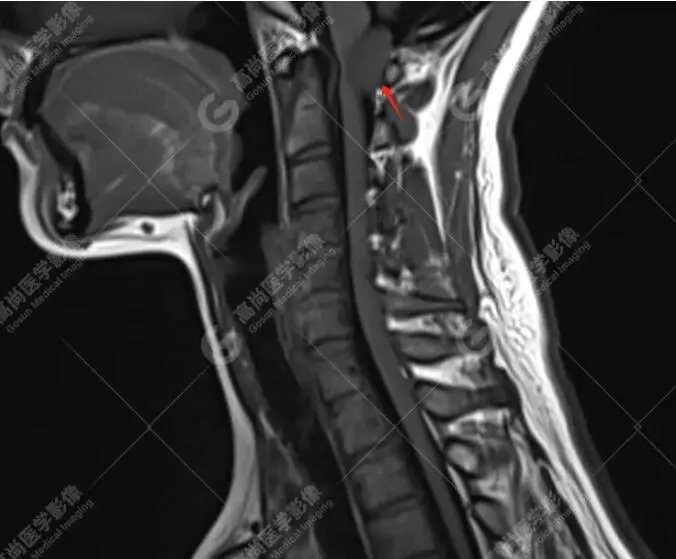

林女士,40岁,左侧头颈部疼痛1年,一直以为只是偏头痛,药物治疗,但效果甚微。后来到我中心做了头颅磁共振平扫;颈椎磁共振平扫+增强,终于发现症结所在。

磁共振图像

T1平扫

检查所见:检查发现其C1椎体-向上枕大孔上部水平椎管髓外硬膜下占位,考虑是脊膜瘤。